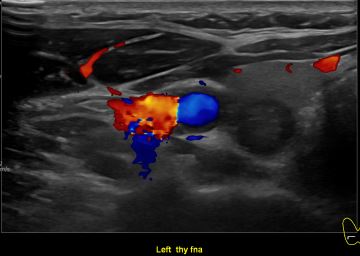

상기환자 외부건진이상소견 세침검사위해 내원하신 50대초반 여성분으로

의심스러운 갑상선 좌엽 결절 세포검사 진행후 갑상선암으로 진단되었습니다